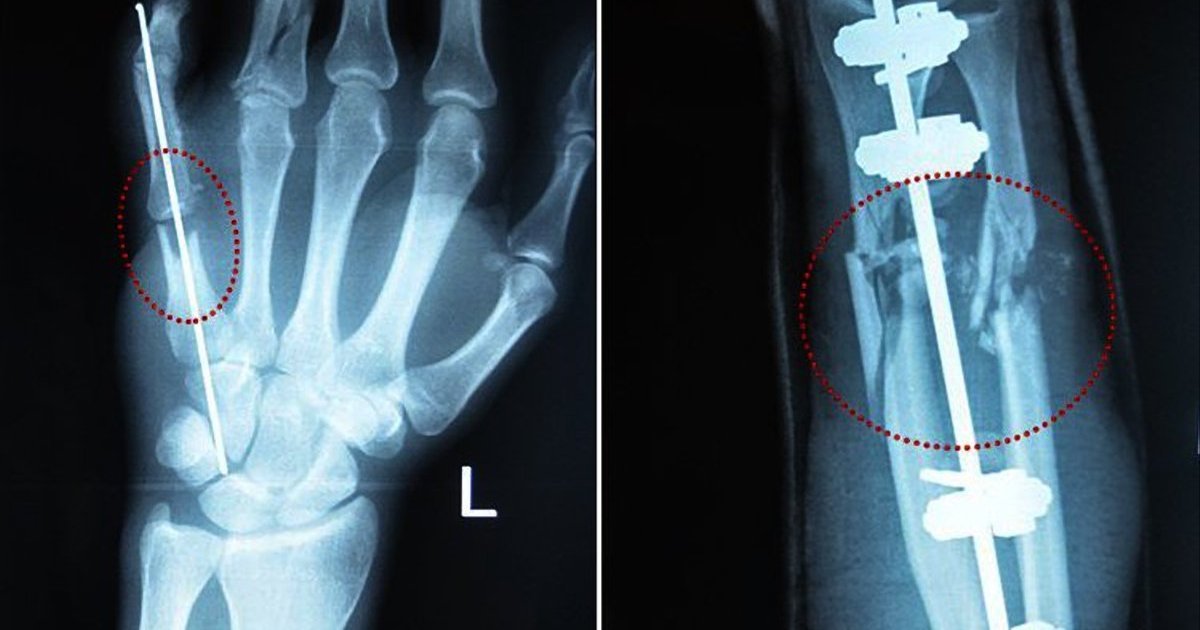

"Евгений же присоединился к проекту относительно недавно. У молодого разведчика тяжело повреждены обе руки и нога. Евгений прошел горячие точки фронта буквально на острие атаки. Во время очередного боя, где противником выступила морская пехота оккупанта, получил значительные ранения. Даже тяжело раненый мужчина пытался продолжить бой, и собратья силой вывели его из-под обстрела. На момент начала лечения Евгений имел повреждены связки правого колена, привычный вывих правого плеча, разбитое правое предплечье, были раздроблены кости левой кисти. В государственных больницах шла речь об ампутации пальцев и фиксировании переломов пластинами, и мужчина обратился к проекту "Биотех-реабилитация раненых".